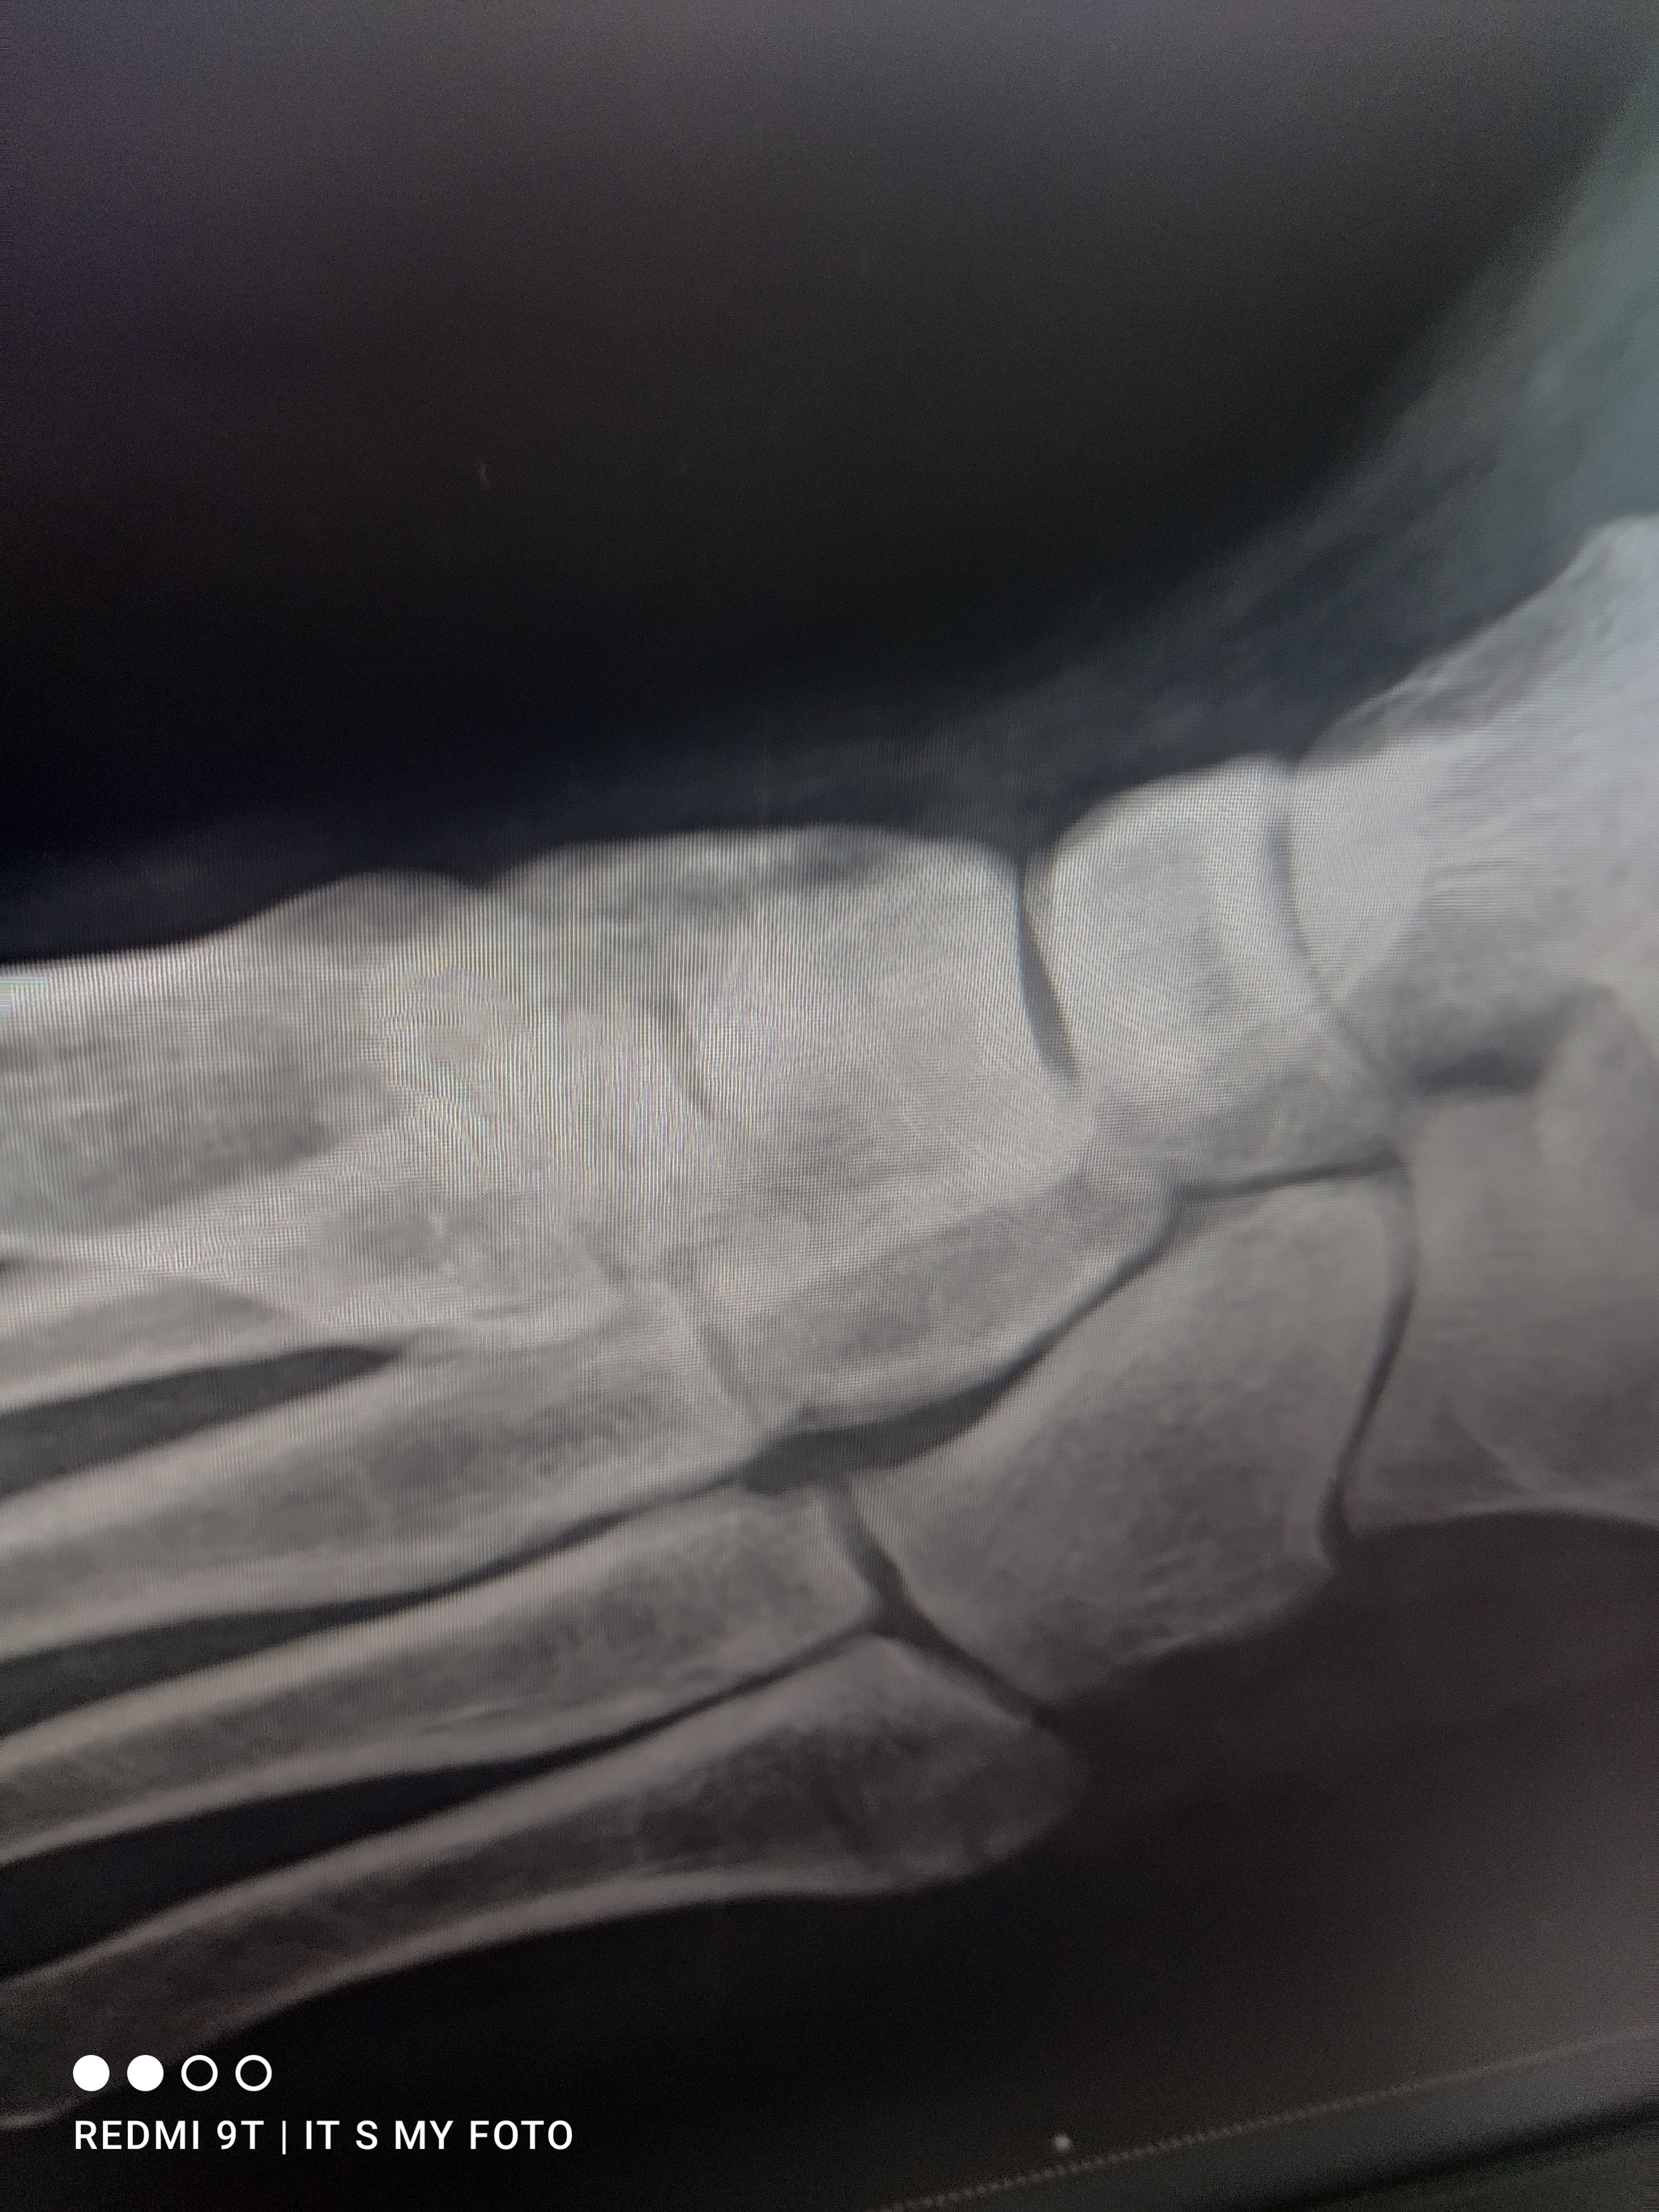

И на обратной дороге на лестнице. Не правильно наступил ,собакин дернул поводок и вот результат

Теперь 3 недели . будем кушать Доширак и мух ловить плевком )